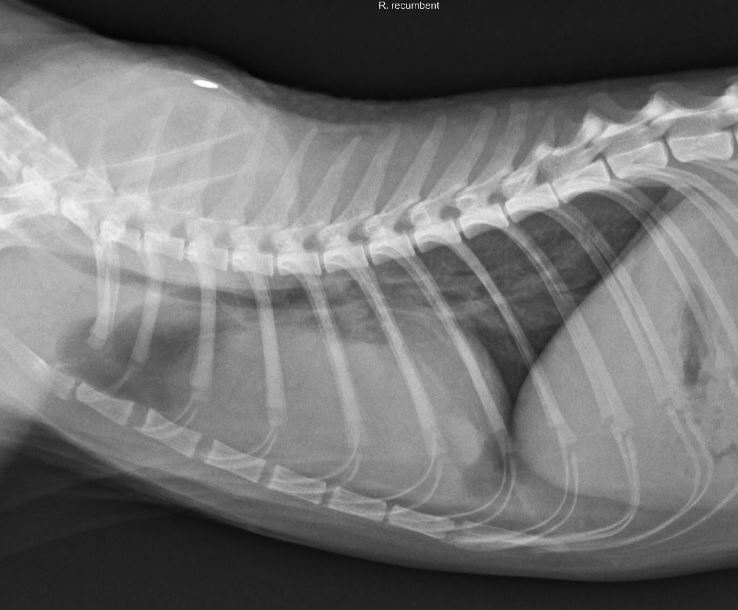

貓胸腺瘤

胸腺瘤是一種相當少見的前縱膈腔腫瘤,其源自於胸腺上皮,並有不同程度的成熟淋巴球及肥大細胞浸潤其中,多發生於9~10歲齡老貓。貓胸腺瘤大多生長緩慢,常常等到腫瘤發展到一定程度時才會出現臨床症狀。